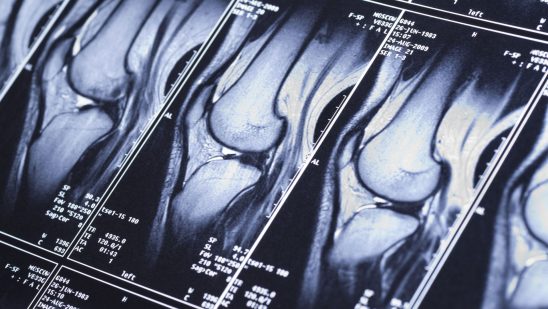

Orthopedics deals with bone, joints, ligaments, muscles, and peripheral nerves. Orthopedics is a word derived from 2 Greek words: Orthos means straight, and paedios meaning a child. Nicolas Andry coined the term in his textbook for the use of exercise, manipulation, and splinting of limbs to treat deformities in children. In the past Orthopedics meant to keep the body straight, usually of the spine. However, this concept is now wide and Orthopedic surgery means to preserve and maintain mobility of the human body in the best way possible. This is achieved by prevention, diagnosis, and treatment of diseases and injuries, with or without surgery, in all age groups.

Orthopedic surgery is usually performed by a team. The team is led by an Orthopedic surgeon, and the team consists of an Anesthesiologist, assistant surgeons, scrub nurses, and an experienced intra-operative radiographer. The operation theatre for performing the surgeries is well lit and well-equipped with intraoperative fluoroscopy (X-ray), lead aprons, drill machines, necessary basic surgical instruments, and even microscopes or endoscopes as the surgery demands.